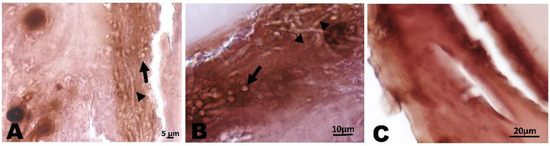

The co-existence of C. albicans and F. oxysporum is clearly visible in the SEM image of the dual-species biofilm (Figure 3). Indeed, it is characterized by a dense network of C. albicans yeast-like cells and elongated fungal hyphae, with a predominance of yeast-like cells.

In Figure 9, the results of the histological analysis performed on G. mellonella larvae infected with the two pathogens and treated with the combination WMR/FLC are reported. It is evident that in the tissues of treated animals, the presence of C. albicans cells and F. oxysporum hyphae was not detectable.

Figure 9. G. mellonella histopathology stained with hematoxylin and eosin. (A,B): C. albicans cells (arrow) and fungal hyphae (arrowhead) in infected G. mellonella larvae. (C): G. mellonella larvae treated with WMR peptide in combination with FLC.